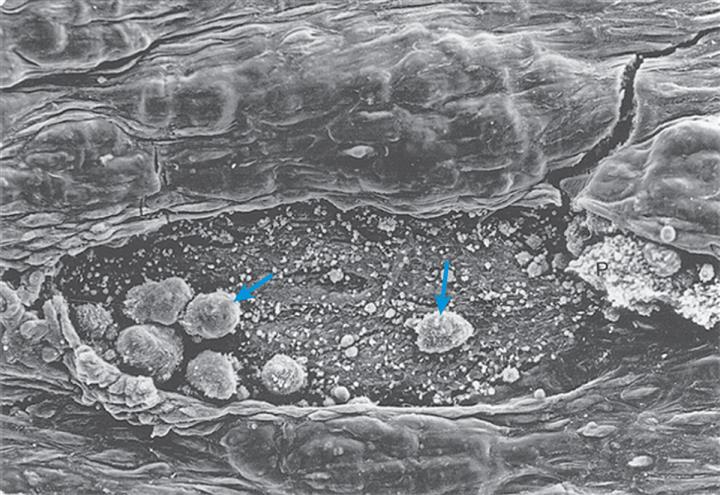

Platelets (thrombocytes) are not true cells, but rather irregularly discoid-shaped cytoplasmic fragments that lack a nucleus and deoxyribonucleic acid (DNA) and are incapable of mitotic division. Platelets are essential for blood coagulation and control of bleeding. They are formed in the bone marrow by fragmentation of very large cells (40 to 100 μm in diameter) known as megakaryocytes. They contain cytoplasmic granules (e.g., dense granules, alpha granules, and lysosomes) and can release adhesive proteins and coagulation and growth factors when stimulated by injury to a blood vessel. Platelets can assume different shapes and form adhesive pseudopodia (long surface extensions) that increase their surface area and promote interconnectedness and adherence to collagen fibers in damaged vascular walls, plugging vascular openings to control bleeding (Fig. 28.5).